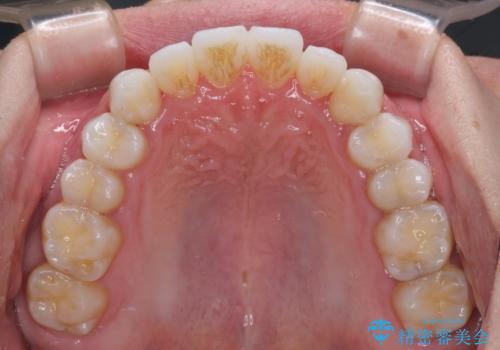

前歯のクロスバイトを改善 インビザラインによる矯正治療

- 前歯のクロスバイトを気にして来院された患者様です。

デコボコやクロスバイトが散見されたため、IPR(歯と歯の間を削る)によってスペースを獲得できるように設計し、インビザラインにより治療を行うこととしました。

上顎側切歯(上の真ん中から2番目の歯)が舌側転位している場合、インビザラインでは仕上げきれない可能性があり、更には無理して動かそうとすると歯髄壊死を起こすリスクが高いと言われています。

安全に治療を行う対策として、インビザラインで歯列を移動する前に、上顎前歯をワイヤー矯正で整え、その後上下歯列をインビザラインにて矯正治療を行うプランを提案しています。

今回は、ワイヤー装置を併用することなく治療を行い、トラブルなく、満足のいく歯列に整えることができました。

矯正治療の途中でホームホワイトニングを併用され、術前とは見違えるほどきれいな口元となりました。